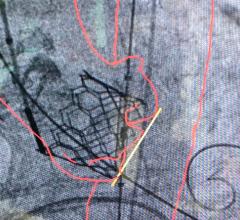

This structural heart channel includes news, videos, podcasts and other content related to diagnosis and treatment of structural heart disease. Topics covered include heart valve repair and replacement, transcatheter aortic valve replacement (TAVR), transcatheter mitral valve replacement (TMVR), transcatheter tricuspid valve replacement (TTVR), left atrial appendage (LAA) occlusion, heart failure interventional device therapies, and closing holes in the heart using, including occlusion of atrial septal defects (ASDs), ventricular septal defects (VSDs) and patent foramen ovales (PFOs).

April 25, 2024 — Atlantic Health System’s Morristown Medical Center treated the first patient in New Jersey using Edward ...

April 23, 2024 — Medtronic plc, a global leader in healthcare technology, today announced the launch of its latest ...

April 9, 2024 — UC Davis Health cardiology team members are among the first in the country to treat patients with tricus ...

April 9, 2024 — People with a small aortic annulus, a part of the heart’s anatomy where the left ventricle meets the ...

April 2, 2024 — Abbott announced that the U.S. Food and Drug Administration (FDA) approved the company's first-of-its ...

March 28, 2024 — Medtronic plc, a global leader in healthcare technology, announced that the United States Food and Drug ...